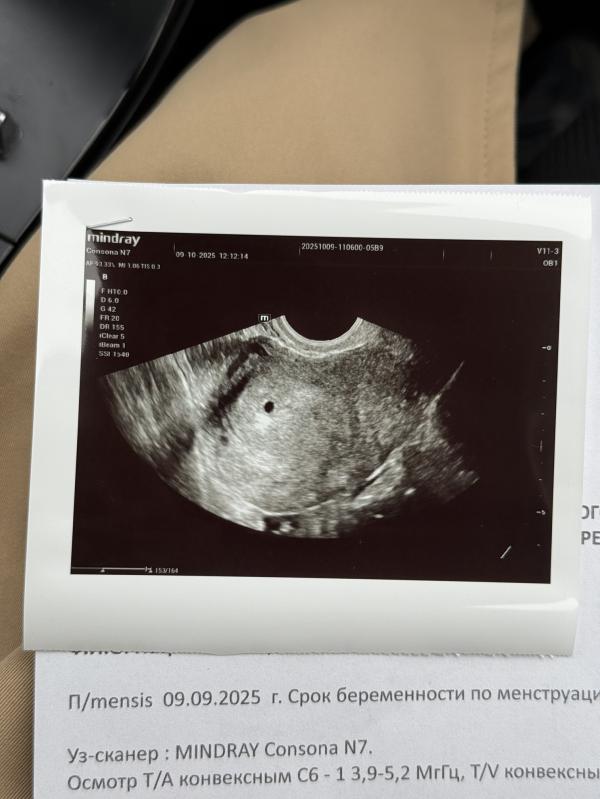

Моему счастью нет придела 🥹🙏🏻

Даже не верится ,что эта точка человечек 💔